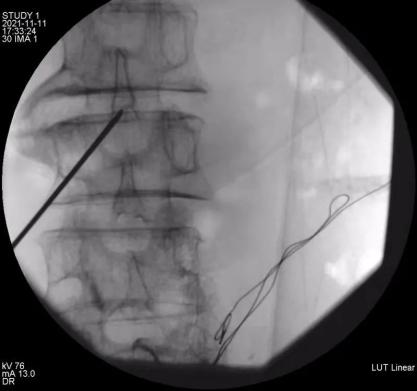

11月9日上午,余斌教授为还先生进行了镇痛泵安装前鞘内吗啡测试,结果显示鞘内吗啡对患者的镇痛效果十分明显。家属决定正式安装鞘内镇痛泵。11月11日下午,余斌教授经过仔细评估和精心准备后,会同新华医院马柯主任、同济医院骨科樊健主任、蔡涛医生一起,为还先生成功实施了该手术。术后镇痛效果良好,当晚还先生就没有了疼痛的折磨,VAS评分降至3分以下。自吗啡泵植入后,每天仅需吗啡0.4mg即可达到满意镇痛效果,阿片类药物副作用明显减少。解决了疼痛,患者的睡眠、饮食和精神状态都得到了极大的改善。

鞘内镇痛泵植入术

余斌教授介绍,鞘内镇痛泵植入术是通过微创手术,将一个可储存吗啡等镇痛药液的微量泵放置在皮下,并通过埋藏在皮下的导管将药液持续不断地输注到蛛网膜下腔,直接作用于中枢神经系统发挥镇痛作用。鞘内镇痛泵的用药量仅为静脉用药的1/100,口服药量的1/300,相比较其他的镇痛方式,其提高了镇痛效果,大大降低了药量,减少了药物不良反应,同时一次加药维持数月,方便长期控制疼痛,患者还可以根据自己疼痛程度自主调节用药剂量,体现了精准化医疗,舒适化医疗的理念。